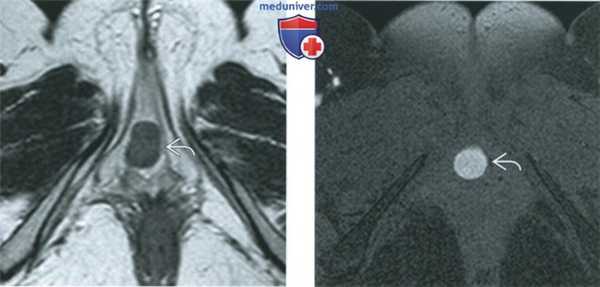

(Слева) При МРТ на Т2-ВИ в аксиальной плоскости у наружного отверстия уретры в переднем отделе входа во влагалище выявляется гипоинтенсивное объемное образование.

(Справа) При МРТ на Т1-ВИ FS в аксиальной плоскости у той же пациентки образование дает гиперинтенсивный сигнал. Локализация и МР-особенности объемного образования позволяют сделать заключение, что оно, скорее всего, является кистой железы Скина, осложнившейся кровоизлиянием.